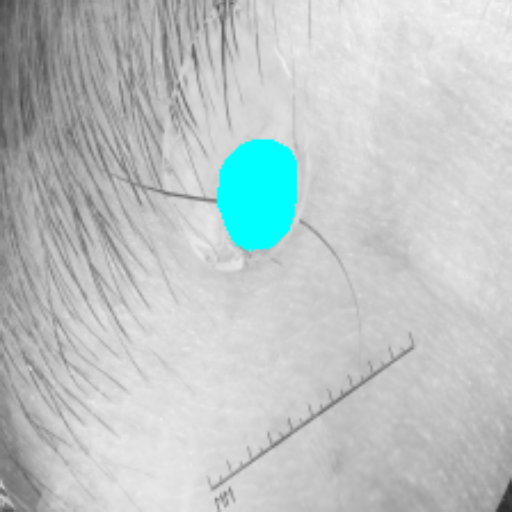

Across BTCV, ACDC, and ISIC17, the comparison methods exhibit varying performance depending on the task and class. For instance, Mamba-Unet struggles to segment multiple organs in BTCV, even misclassifying certain classes as others. In the ACDC dataset, both TransUnet and Mamba-Unet perform poorly in segmenting the three classes. In the last column (ISIC17), Swin-Unet oversegments the skin lesion compared to the ground truth. Unlike the comparison models, our approach consistently delivers effective segmentation across different tasks and datasets.

Slice GT Unet TransUnet Mamba-Unet Swin-UMamba MambaCAFU-V1

Figure 3: Visual comparison of segmentation examples from Synapse (first two examples), BTCV (3-4 examples), ACDC (5th example) and ISIC17 (last example). Columns: input slice, ground truth, Unet, TransUnet, Mamba-Unet, Swin-UMamba, and MambaCAFU-V1.